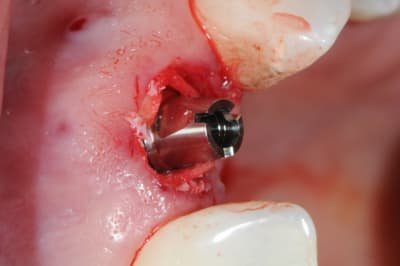

Une extraction avec mise en charge immédiate qui ne c'est pas bien passée (mauvaise ostéo-intégration), donc dépose (4x140mm) et repose d'un 4.6x140, et ROG car pas d'os vestibulaire.

MP3 (OstéoBiol) et membrane évolution std 30x30mm (OstéoBiol)

Produit sympa qui ne laisse pas de particule comme le BioOss.

Pas de pin ou vis, seulement sutures.

en réalité la membrane est glissé sous le périoste qui est décollé, mais pas déplacé.

Je travaille ta technique en essayant de simplifier, en gros la ROG pour les nuls.:-))